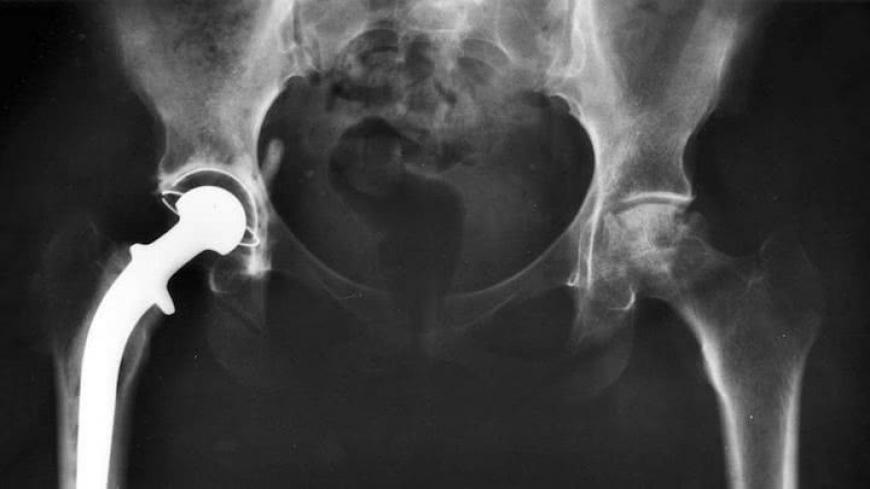

Stryker Orthopaedics recently issued a hazard alert warning doctors and patients of potential side effects that may be caused by seven models of Stryker V40 femoral heads, which are used in metal-on-metal (MoM) hip replacement procedures.

Many companies have ceased producing MoM hip replacements altogether because of the kinds of risks outlined in the alert. When the metal head rubs against the metal socket, metal particles can be released into the bloodstream, leading to cobalt chromium poisoning.